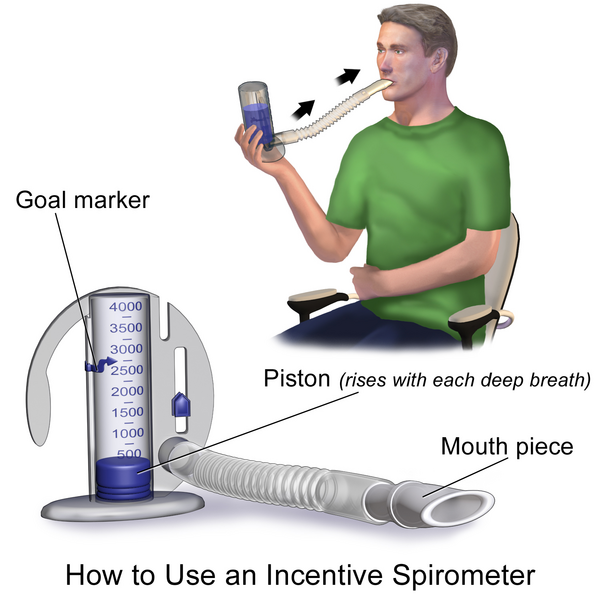

2 – Diagnostic Tools – Spirometry, Arterial Blood gas, Oximeter, Exercise Tolerance Testing, X-ray, Bronchoscopy, Culture and Sensitivity Tests, Sneezing Reflex, Coughing Reflex,

- Secretion Control – In patients with respiratory failure there is often high production of sputum secretions that can cause poor gas exchange and lead to mucus plugging or lung failure. To prevent this from happening simple strategies like deep breathing, chest physiotherapy or mucolytic medications can help.